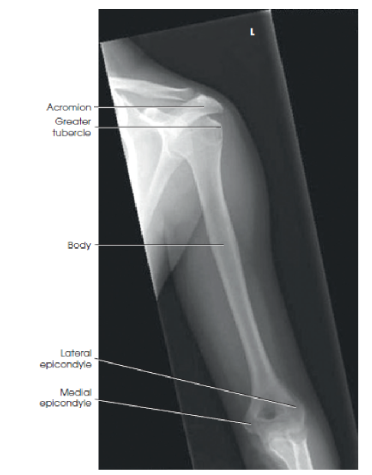

What are the proximal anatomical structures of the humerus?

The head, anatomic neck, surgical neck, greater tubercle, and lesser tubercle.

Name the distal anatomical structures of the humerus.

The medial epicondyle, lateral epicondyle, trochlea, capitulum, coronoid fossa, and olecranon fossa.

What are the evaluation criteria/structures shown for a Lateral humerus image?

Elbow and shoulder joints visible, but slightly distorted due to beam divergence

superimposed humeral epicondyles

lesser tubercle in profile on medial aspect

greater tubercle superimposed over the humeral head

bony trabecular detail and surrounding soft tissues